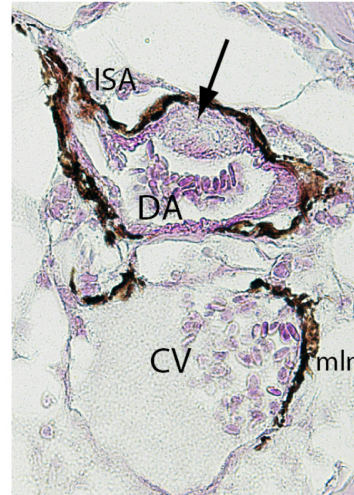

ÎÄÏ×ÖÐ˵µÄÊÇÓÃVGȾɫµÄ·½·¨£¬È»ºó²éÁËVG ȾɫµÄ×ÊÁÏ˵VG·¨Ê¹½ºÔ­ÏËάºìÉ«£¬¼¡ÏËά»ÆÉ«£¬Ï¸°ûºË»ÒºÚÉ«£¬µ«ÊÇÎÄÏ×ÖеÄͼƬûÓз¢ÏÖÓкìÉ«»ÆÉ«µÄ¡£ÇëÎÊͼƬÊÇVGȾɫºóµÄ£¿ÔõôÀí½âͼƬȾµÄÉ«£¿»¹ÓÐÎÄÏ×ÖÐдµ½Ò»¾ä»°£¨²¨ÀËÏߣ©ËµÏÈÒªÓÃbright field ÏÔ΢¾µ¹Û²ìûÓÐȾɫµÄ²¿·Ö£¬ÔõôÀí½â£¿ÓÐʲô×÷Óã¿